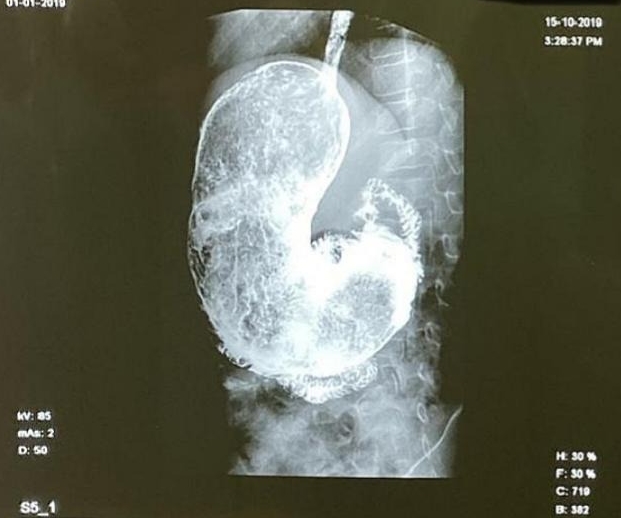

He then had an esophagogram (a specialised X-ray) which identified the mass as a gastric trichobezoar – a giant hairball and mass of indigestible materials –– and he was admitted for surgery.

The shocking case was recounted in a medical journal, where doctors described it as “comma-shaped”.